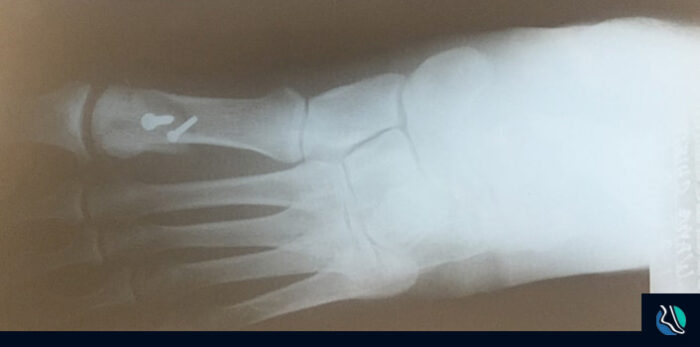

I have been suffering from arthritis in my left great toe for many years. When wearing certain shoes, my big toe joint would swell and turn red. To ease the pain, I wore orthotics and stiff soled wide shoes. Cortisone injections and anti-inflammatory medication also became an essential part of my daily routine. All of…